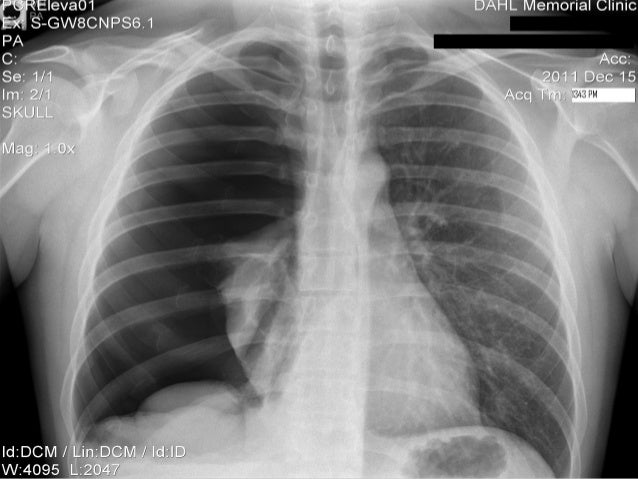

Pneumothorax Chest Tube : CXR showing right sided chest tube and resolution of pneumothorax. | Download Scientific Diagram / Collapsed lung (pneumothorax)—this occurs when air has built up in the area around the lungs (the pleural space) from a leak in the lung.

Pneumothorax Chest Tube : CXR showing right sided chest tube and resolution of pneumothorax. | Download Scientific Diagram / Collapsed lung (pneumothorax)—this occurs when air has built up in the area around the lungs (the pleural space) from a leak in the lung.. How does a chest tube work for a pneumothorax? Collapsed lung (pneumothorax)—this occurs when air has built up in the area around the lungs (the pleural space) from a leak in the lung. Why do i need a chest tube? Chest tube insertion for pneumothorax or hematothorax.this video will show you how to insert a chest tube for a pneumothoraxthis patient has multiple rib fra. How long does it take to recover from a pneumothorax?